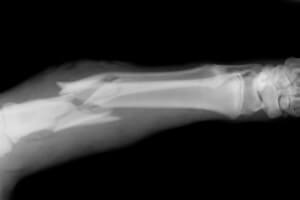

- Средней трети. Сопровождается острой болью и появлением гематом. Отломки кости вкалываются в сосуды, что вызывает внутреннее кровотечение. Есть вероятность, что травма средней трети со смещением приведет к уменьшению длины травмированной конечности.

- Нижней трети. Болевые ощущения незначительны, сконцентрированы в колене и вызывают его отек. У пациента конечность вытягивается вдоль собственной оси, отломанные костные части тоже вызывают обильную потерю крови.

Лечение включает использование разных хирургических элементов (вытяжение, штифты.).

В проксимальной части кости наибольшее повреждение получает шейка, восстановление которой требует операции. Для молодых людей используют методы консервативной терапии и ношение гипса на протяжении 8 — 10 недель.